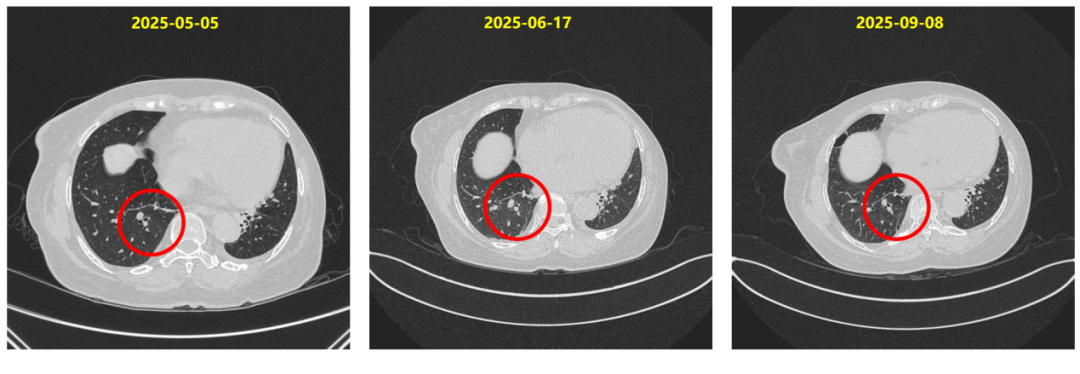

2025-03-18复查胸部CT提示:右肺下叶炎症考虑,局部较前明显,建议复查。

2025-03-19开始予甲泼尼龙(12mg po bid)治疗[等于0.5mg/(kg?d)泼尼松],10天后改为(8mg po bid)。

2025-04-09复查胸部CT:肺下叶炎症考虑,较前吸收,建议复查。

2025-04-10予甲泼尼龙(4mg po bid)治疗,2025-04-20至2025-04-30予甲泼尼龙(4mg po qd)治疗。

2025-05-05复查胸部CT:前片右肺下叶炎性灶基本吸收。

ILD完全控制,恢复T-DXd治疗:

患者于2025-05-06恢复德曲妥珠单抗(300mg,q3w)靶向治疗。

同时在T-DXd治疗过程中,患者于第11周期后出现右肺下叶炎症,经影像学评估确诊为1级间质性肺病。我们立即启动大剂量甲泼尼龙治疗,后逐步减量,ILD在22天内明显缓解,45天内基本消失。在确保ILD完全控制后,我们于2025年5月再启动T-DXd治疗,患者持续获益,影像学评估持续PR。该病例充分体现了在T-DXd使用过程中ILD这一关键不良反应的可管理性。通过早期识别、及时干预、规范减量和再挑战,患者不仅安全度过风险期,还继续从T-DXd治疗中持续获益。

△DB-04研究在HR+亚组和全人群中的治疗疗效

同时,发生ILD是T-DXd治疗中需要关注的不良事件。本例患者接受T-DXd治疗过程中,于第11周期后出现了1级ILD,影像学表现为右肺下叶局限性炎症,无临床症状。团队在第一时间识别并启动激素干预(甲泼尼龙12mg bid),22天后复查CT显示炎症吸收,随后规范减量,约1个月后CT证实完全吸收。这一过程完全符合既往中华肿瘤杂志发表的《抗肿瘤药物相关间质性肺病诊治专家共识(2022)》[2]的分级管理原则。

ILD后T-DXd再挑战的可行性与安全性

本例患者ILD完全缓解后,于停药49天重启T-DXd治疗,剂量不变,后续随访多月余未见ILD复发,疗效持续。这一管理策略与2025年ASCO发布的真实世界研究数据高度一致[3]:该研究提示,患者出现1级ILD后,经规范治疗可尝试再挑战,患者仍能获得持久临床获益;同时,使用类固醇治疗可显著加速ILD影像学改善;而接受再挑战的患者中,复发性ILD的发生率较低,且大多为1级事件,未见5级事件发生。这些数据进一步支持了ILD患者应用T-DXd治疗再挑战策略的可行性与安全性。